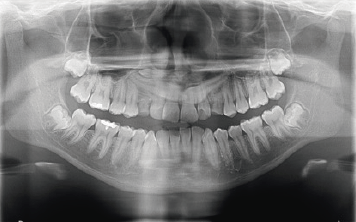

Es la rama de la odontología encargada del diagnóstico y tratamiento quirúrgico de las alteraciones en los tejidos duros y blandos de la boca como patologías infecciosas, tumorales y de malformaciones bucales y maxilofaciales, utilizando como ayudas diagnósticas la imagenología, la histopatología y pruebas de laboratorio clínico.

El odontólogo especialista en esta área posee el conocimiento y la destreza para toma de biopsias, realización de tratamientos de urgencias, manejo de alteraciones de la boca como: frenillos traccionantes, dientes retenidos o incluidos, cirugías pre protésicas, cirugías maxilo facilaes y reconstructivas.